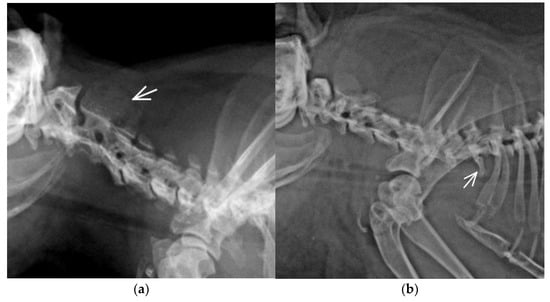

3.2. Congenital Vertebral Anomalies

| CTV | Unilateral rudimentary rib | CT junction | C7+CTV/Th12/L6/ S4/Cd6 | 1 | 0.42 | 3.33 | M |

| Block vertebra, TTV | Block C2-C3, TTV unilateral rudimentary rib | Cervical, TL junction | C8(blockC2-C3)/Th12+TTV/ L5/S4/Cd6 | 1 | 0.42 | 3.33 | F |